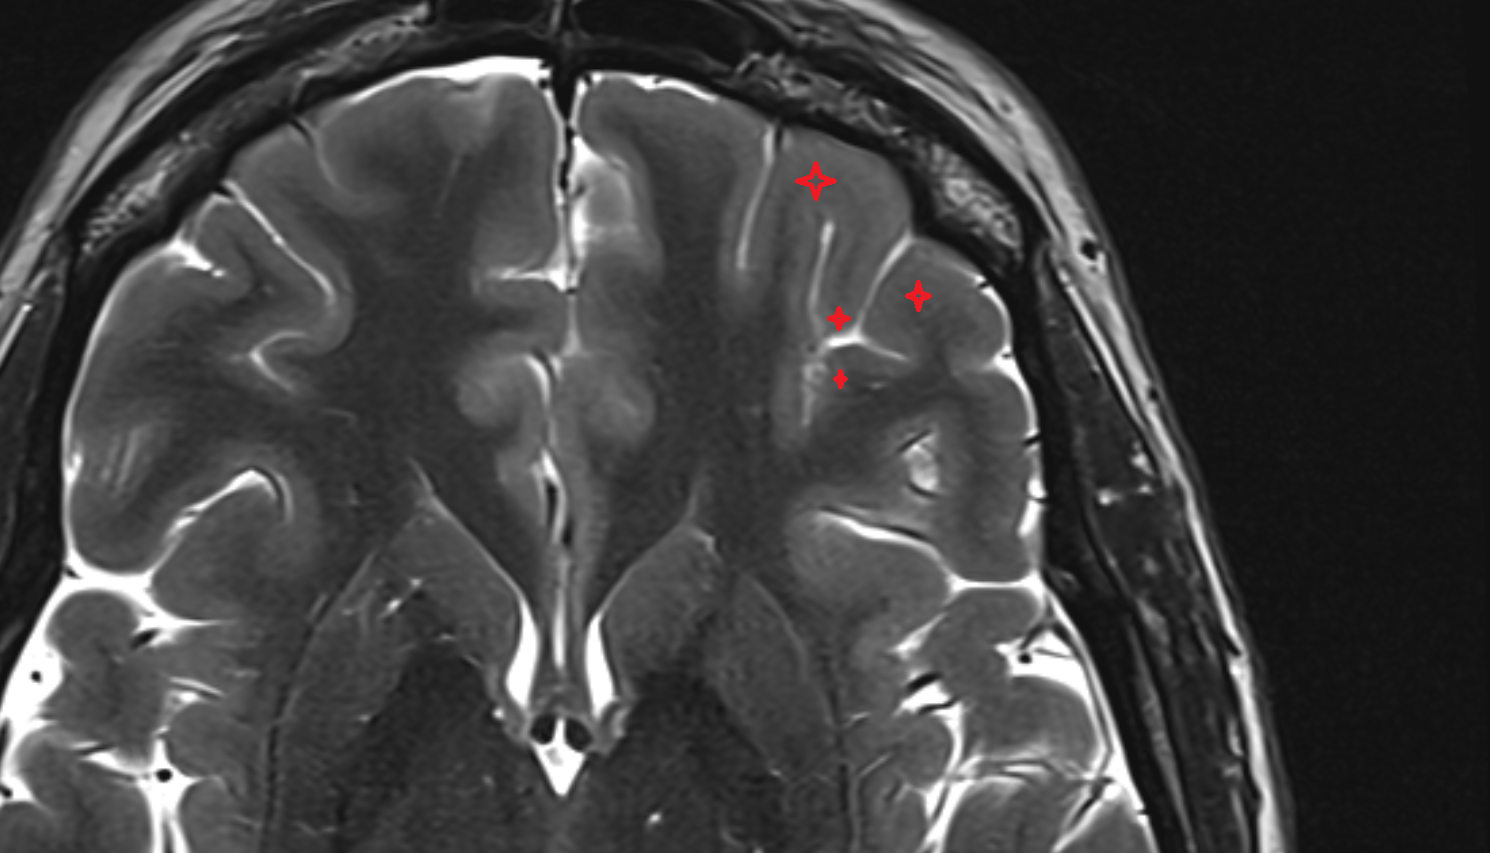

- Central sulcus